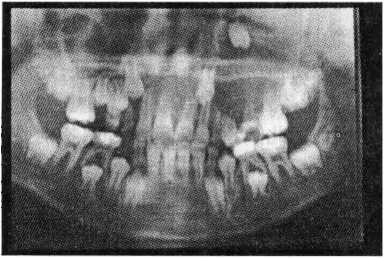

兒童牙科,經常見到醫生給患了齲病、牙髓及根尖周病等乳牙拍X線牙片,有些家長非常不理解,看牙病還要拍X線片,這是為什麼?維港口腔牙醫介紹,醫生從X線牙片中可以瞭解以下情況:

(1) 乳牙齲病的深度:觀察齲病與牙髓腔的關係,是否近髓,是否穿髓,以便擬定對解病的治療方案。

(2) 乳牙根分叉及根尖周的病變:觀察乳牙牙髓病及根尖周病的根分叉有無破壞,觀察乳牙根尖周有無病變以及病變破壞範圍的大小,以便擬定治療方案及預測療效。

(3) 乳牙根吸收的程度:通過X線片能觀察到乳牙根的吸收程度,是生理性吸收,還是病理性吸收。根據牙根吸收的程度,醫生決定該牙拔還是留,推測乳恒牙替換的大概時間等。

(4) 觀察恒牙胚的情況:在乳牙X線片中醫生能觀察到恒牙胚的發育程度、所處的位置、牙囊是否完整、乳牙根尖周的炎症是否波及恒牙胚,同時還可以觀察到恒牙胚缺失與否。

(5) 觀察治療的情況:乳牙根管治療後,觀察乳牙根管充填是否超填、平填及欠填等。

總之,在乳牙治療的過程中照X線片是為了給患牙作出正確的診斷、擬定合理的治療方案以及觀察治療情況。